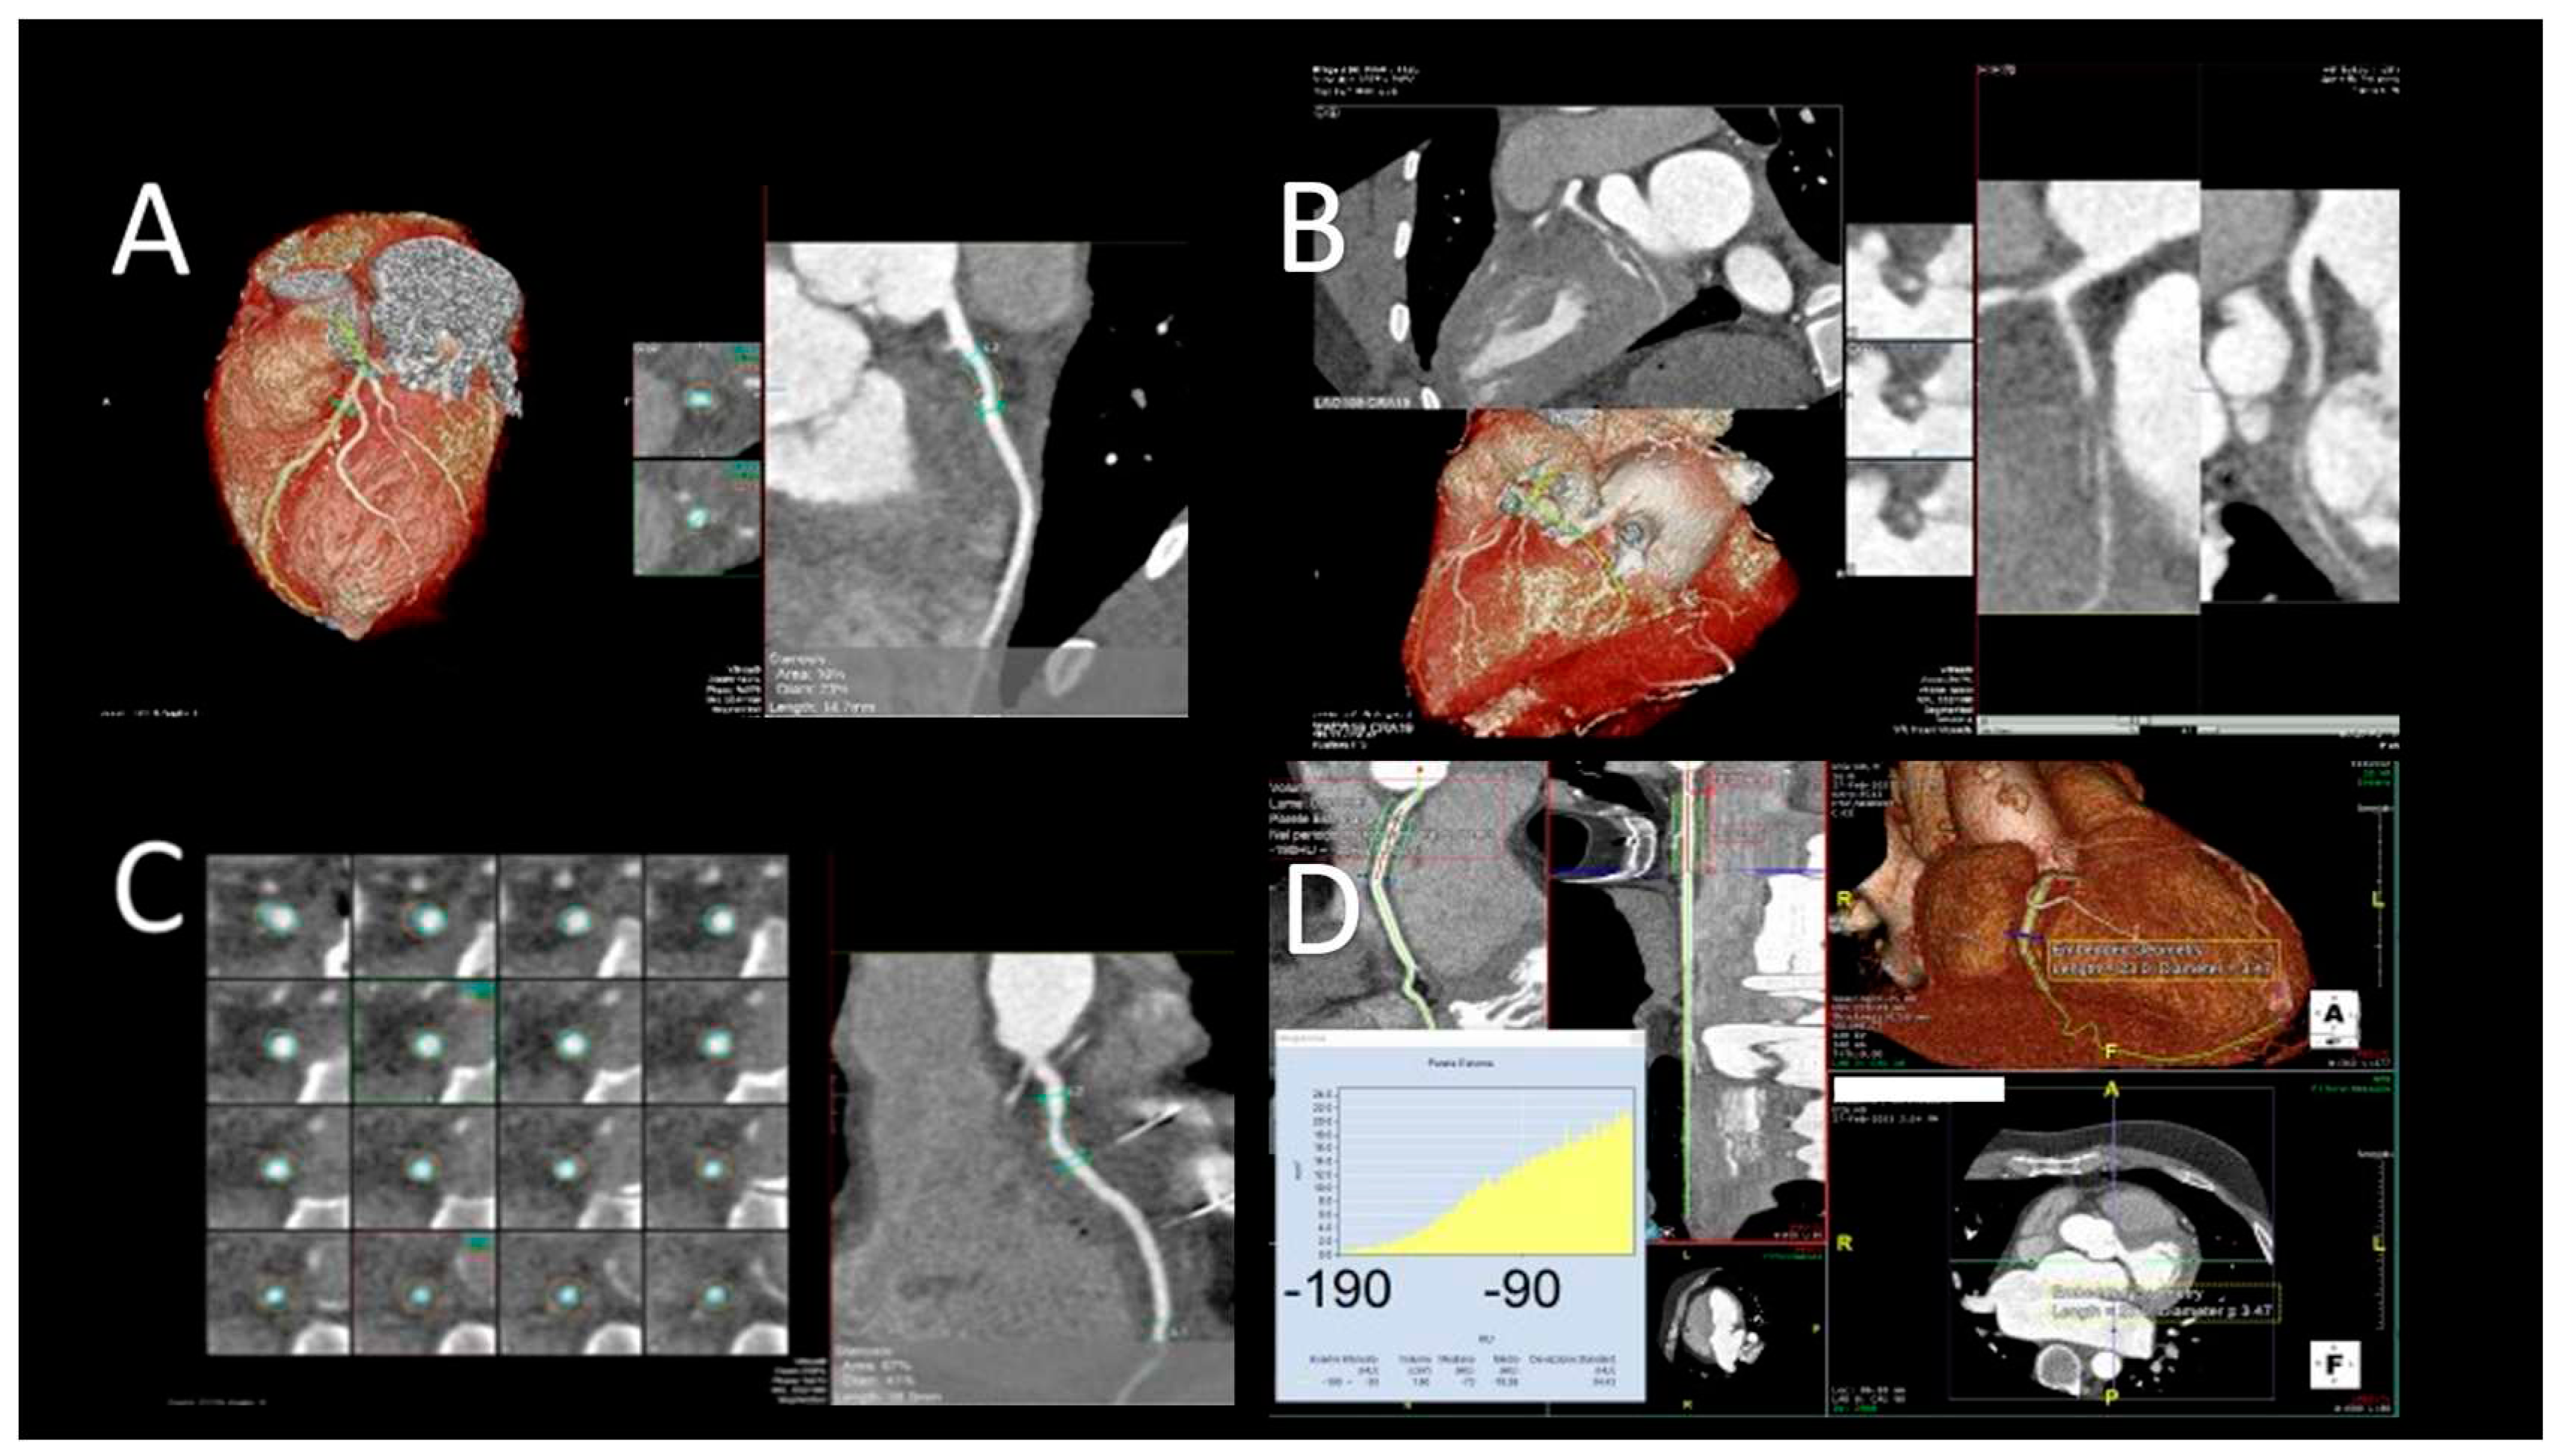

Figure 4. Evaluation after LVAD assist device. A) TTE evaluation (PLAX) shows normal position of IVS and the inflow cannula; B) TTE (PLAX) of LVAD patient, showing incorrect right-convex position of the IVS; C) TTE evaluation (PLAX) of LVAD patient, showing incorrect left-convex position of the IVS; D) CCT showing hematoma around LV cannula; E) CCT showing small LV apical thrombus.

1. LV size and function. The most reproducible is the LV internal diameter end diastole (LVIDd) from the 2D parasternal long axis image. The LVIDd may be paradoxically smaller than the Left ventricular internal diameter end systole (LVIDs), and this is an important finding, as it is associated with excessive LVAD unloading and/or severe RV dysfunction. The evaluation of LVEF can demonstrate possible LV worsening or recovery. A possible complication to evaluate is LV suction with induced ventricular ectopy; this condition is due to LV underfilling that causes impact of inflow cannula with LV endocardium, and the solution is speed turndown.

2. Position of interventricular septum (IVS) and cannulas. The end-diastolic IVS position should be neutral, leftward-shifted or rightward-shifted. A leftward shift can be due to elevated RV end-diastolic pressures, reduced LV preload, or LV over-decompression resulting from excessive LVAD speed. A rightward IVS shift is generally due to elevated LV end-diastolic pressures resulting from an inadequate LVAD speed setting, pump dysfunction, severe AR, or an increased LV afterload. The inflow cannula can be evaluated in the parasternal or apical TTE views. Is important to reveal the cannula’s location and orientation in relation to IVS and other LV structures. The colour Doppler interrogation should demonstrate a one directional, laminar flow from LV to inflow cannula without turbulence or regurgitation. At continuous Doppler interrogation, the flow should have peak velocity between 1 and 2 m/sec; a higher velocity may suggest inflow obstruction.

3. Aortic valve (AV) opening and AR severity. It is important to evaluate the presence e the degree of AV opening because it is determined by different parameters like LVAD speed, LV native function, volume status and peripheral vascular resistance. LVAD types differ in aortic valve opening pattern, especially for intermittent low speed phase (es. 9 seconds for Jarvick). It is recommended LVAD speed to be set to allow at least one intermittent opening of the AV. The AV opening is assessed with M-Mode. In patient with very depressed LVEF, AV opening may not occur. When AV remains closed, aortic root thrombus should also be excluded. Another risk in LVAD patients is the development of AR, which is not uncommon after LVAD implantation. Assessment of its severity is partly based on careful colour Doppler analysis in the parasternal long-axis view.

4. RV size and function. During TTE follow-up, RV function must be carefully evaluated. The shift of the IVS to the left side by LVAD may reduce the IVS contribution to the RV contraction. Furthermore, increased venous return created by increased cardiac output from the LVAD may worsen the RV function. This increased workload is a concern for worsening RV function that LVAD patients may already have. The classical criteria for RV dysfunction included the following parameters: TAPSE < 17 mm, tricuspid annulus systolic peak velocity (S') velocity < 10 cm/s and RVFAC < 35% (16). Nevertheless, the evaluation of RV function is challenging also because correlation between RV systolic function and TAPSE and/or S' should be considered weaker after cardiothoracic surgery.

5. Evidence of intracardiac thrombi. Recent studies on patients implanted with new generation LVAD suggest that the LV may be a relevant site of local thrombosis and cardioembolism. Pump speed, AV opening, cannula location, and orientation are important determinants of LV flow that are drastically disrupted in LVAD patients, leading to blood stasis or abnormally large shear stresses (Figure 4) (43).

2.3.4. Role of cardiac computed tomography in LVAD patients

CMR is contraindicated in patients with LVAD; therefore, CCT scan represents an opportunity for non-invasive evaluation of the function of the device and its complications (45-47). A limitation of echocardiography in patients with LVAD is the incomplete visualization of the outflow cannula; the latter is well seen with the help of the CCT scan. During the follow-up, CCT can reveal complications such as compression of the right ventricle (due to pericardial clots), thrombosis, malposition and kinking of the outflow cannula. Indications for CCT in LVAD patients include suspicion of: